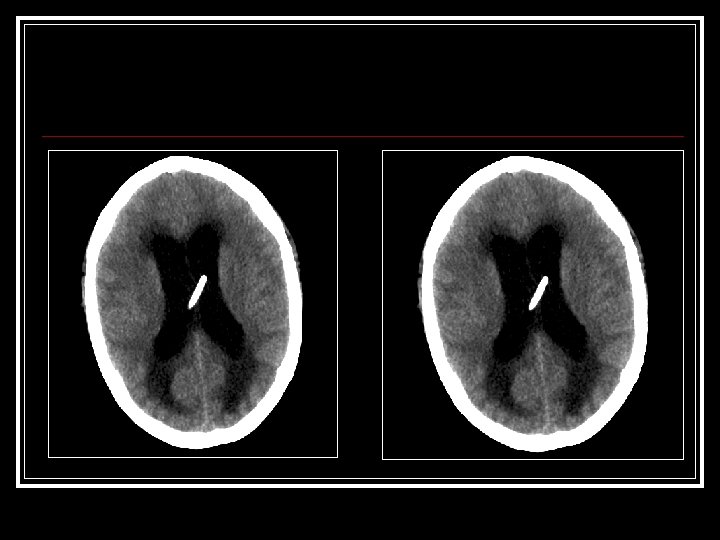

Red Deer Hospital [cont’d] n n n Next 24 H: extubated, more alert & lucid EKG: T-wave changes Echo: akinetic apex TNi 7. 11 (0 -0. 10 ug/L) (>1. 5 ug/L= MI) CK 1751 CT head: Reported as Normal Pt transferred to FMC Cardiology Dx: MI on Nitro drip and Heparin

CCU: n Gets Repeat CT

March 22 [cont’d] n n n Neuro. Surgery Consulted ? Shunt Malfxn Initial exam: Intub, withdrawing disconjugate gaze Drain off 20 cc via shunt reservoir Pt immediately awakes, begins reaching for ETT Cannot palpate distal shunt got AXR: